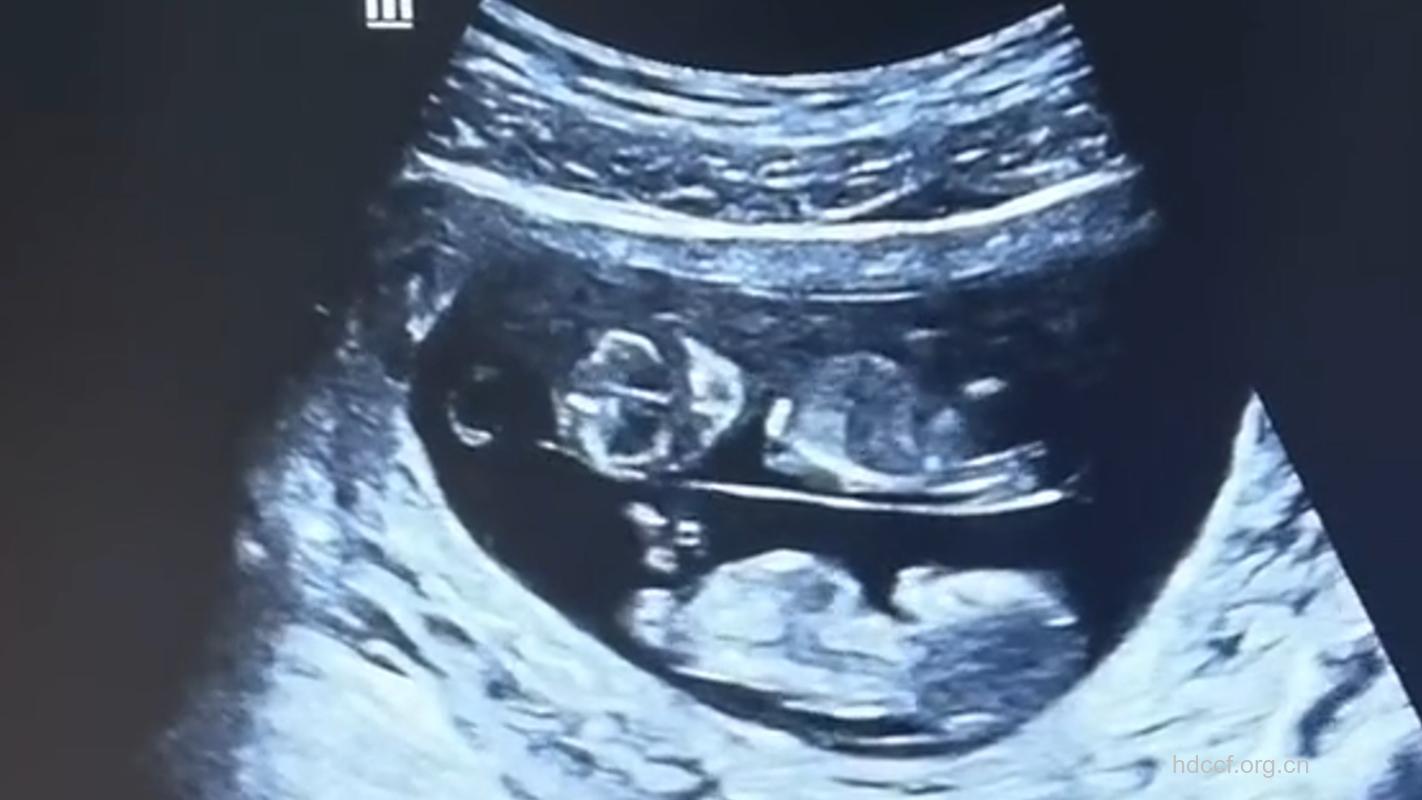

味蕾:胎儿们的味蕾正在发育。

肺:胎儿们的肺部正在发育呼吸“树”的“分枝”,和负责分泌表面活性剂(一种有助于肺部肺泡更易膨胀的物质)的肺部细胞。

子宫:现在你的子宫顶部大约高出肚脐7.5厘米。